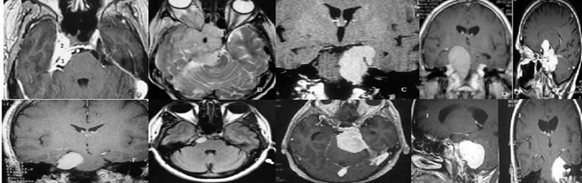

Se utilizan tres abordajes quirúrgicos principales en el manejo de los meningiomas petroclivales: abordaje pterional y sus variantes fronto-orbito-cigomático y pre- temporal, abordaje petroso y sus variantes petrosectomía posterior, anterior o total - “double petrosal approach”, y abordaje retrosigmoideo que se pueden combinar.1,28,29,38-48 Aunque los abordajes endoscópicos endonasales extendidos han evolucionado para controlar algunos meningiomas de la base del cráneo, especialmente los meningiomas de línea media del borde anterior del agujero magno, la posición del nervio abducente en el clivus, la consistencia endurecida de la mayoría de los meningiomas y, en menor medida, la extensión lateral de estos tumores en la fosa posterior, son factores limitantes para este procedimiento cuando se busca la resección máxima con baja o nula morbilidad.(41,29) El organigrama de decisión sobre cuál abordaje elegir puede consultarse en un estudio anterior.(28) Para racionalizar la elección del abordaje dividimos el clivus en tres tercios: tercio superior (del proceso clinoideo posterior al conducto trigeminal), tercio medio (del conducto trigeminal agujero yugular) y el tercio inferior, debajo del agujero yugular y correspondiente al borde anterior del agujero magno

Figura 2: El estudio de la posición del tumor en el clivus, y la extensión o no de éste en la fosa media, sirve para decidir el abordaje. Para los tumores con un componente solo en el clivus superior, se utilizó un abordaje pterional pretemporal, abriendo la muesca de la carpa y eliminando el tumor del clivus superior que estaba comprimiendo el nervio trigémino y causando neuropatía (A). Para este meningioma esfenopetroclvial anaplásico se utilizó el abordaje craneo-órbito-cigomático con petrosectomía anterior con extirpación tumoral. El paciente se sometió previamente a cirugía con ojo congelado (frozen eye) (B). El abordaje petroso posterior (pre-sigmoide supra / infratentorial) se usa para meningiomas petroclivales con extensión tumoral en la fosa media (C, D, E). Para los meningiomas petroclivales localizados completamente en la fosa posterior, el abordaje retrosigmoideo es suficiente independientemente del tamaño del tumor (F, G, H, I, J).

El abordaje retrosigmoideo es simple y fácil de realizar en comparación con los enfoques petrosos. Está indicado cuando el tumor se encuentra principalmente en la fosa posterior, con una pequeña extensión en la fosa media y la porción posterior del seno cavernoso (figura 2). Este abordaje permite alcanzar los tres tercios del clivus. Las supuestas desventajas son la mayor distancia entre el cirujano y el tumor en relación con los abordajes petrosos y la mayor retracción del cerebelo. Sin embargo, estas desventajas son menos evidentes hoy en día debido a la mayor flexibilidad y dinámica de los microscopios quirúrgicos modernos y al posicionamiento de la cabeza girada en posición supina, lo que hace que el cerebelo se mueva lateralmente por gravedad, sin necesidad de retracción, respectivamente. Para tumores de 3 cm o menos, solo hemos utilizado el abordaje suboccipital con excelentes resultados (figura 14). Aunque los abordajes petrosos están reservados para tumores más grandes del clivus medio y superior, el abordaje retrosigmoideo alcanza la extensión completa del clivus. Se debe tener en cuenta la preferencia personal y algunos neurocirujanos optan por la petrosectomía en prácticamente todos los casos.(8)

El meningioma petroclival no debe confundirse con meningioma petroso o tentorial. El meningioma petroclival tiene una inserción más anterior y medial en el clivus. Prácticamente todos los meningiomas tentoriales o petrosos se pueden resecar utilizando el abordaje retrosigmoideo.

Entre los meningiomas de la fosa posterior, la variante petrosa o tentorial tiene un origen tumoral posterior a la fisura petroclival. En éste, los nervios craneales están desplazados antes que el tumor, lo que generalmente reduce el riesgo de morbilidad quirúrgica en comparación con el meningioma petroclival. El abordaje suboccipital suele ser suficiente para los meningiomas tentoriales ubicados en la fosa posterior,26,27 y las lesiones pueden considerarse menos complejas que las petroclivales.